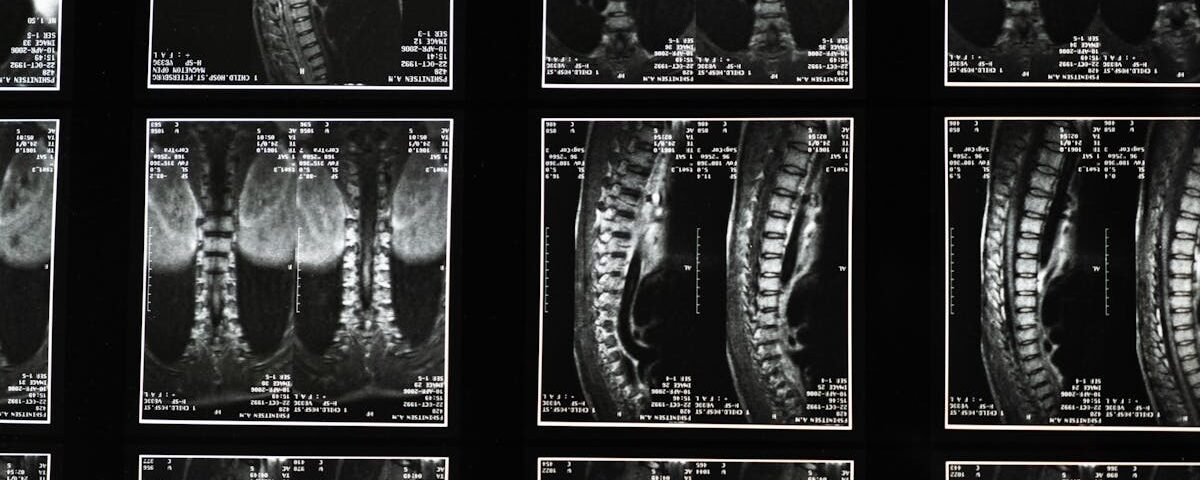

La sciatalgie désigne une douleur qui suit le trajet du nerf sciatique, allant de la colonne vertébrale jusqu’à la jambe. Les symptômes incluent une douleur intense, des sensations de brûlure, des picotements ou des engourdissements. Ces douleurs peuvent résulter de divers facteurs, souvent liés à des problèmes de disques ou de vertèbres.